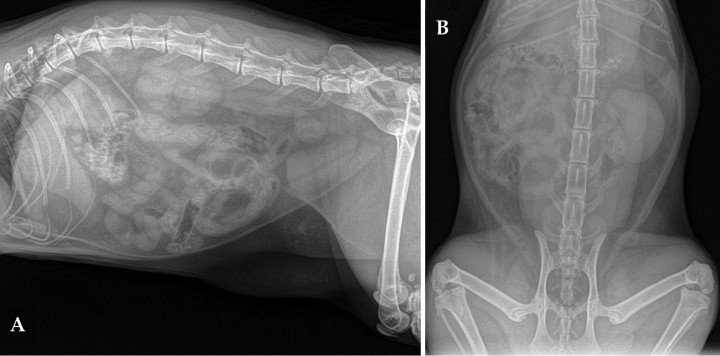

Se hizo un estudio radiológico del abdomen, con proyecciones lateral derecha (LD) y ventrodorsal (VD) (Fig. 1).

<p>(A) Proyección lateral derecha. (B) Proyección ventrodorsal de abdomen de una gata común Europeo de 2 años con un cuadro de hematuria.</p>

(A) Proyección lateral derecha. (B) Proyección ventrodorsal de abdomen de una gata común Europeo de 2 años con un cuadro de hematuria.